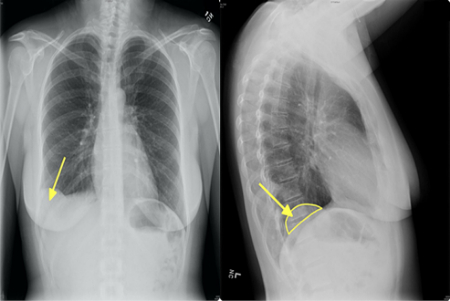

هامارتوماها اغلب به طور اتفاقی در تصویربرداری برای مشکل دیگری کشف می‌شوند. برای تأیید تشخیص ممکن است نیاز به آزمایش‌های تصویربرداری زیر باشد:

• سی‌تی اسکن (CT scan)

• رادیوگرافی (اشعه ایکس)

3. هامارتومای ریه چقدر شایع است؟

شایع‌ترین هامارتومای خوش‌خیم ریه است (حدود ۷۰–۸۰٪ تومورهای خوش‌خیم ریه).

بیشتر در بزرگسالان ۴۰–۶۰ سال دیده می‌شود و در مردان شایع‌تر است.

4. آیا هامارتومای ریه باید عمل شود؟

اگر کوچک باشد و علامتی نداشته باشد → معمولاً فقط پیگیری با سی‌تی اسکن هر ۶–۱۲ ماه. اگر بزرگ‌تر از ۲.۵ سانتی‌متر باشد، در حال تومور باشد یا علائم (سرفه، تنگی نفس) بدهد → جراحی (معمولاً با VATS یا جراحی کم‌تهاجمی).